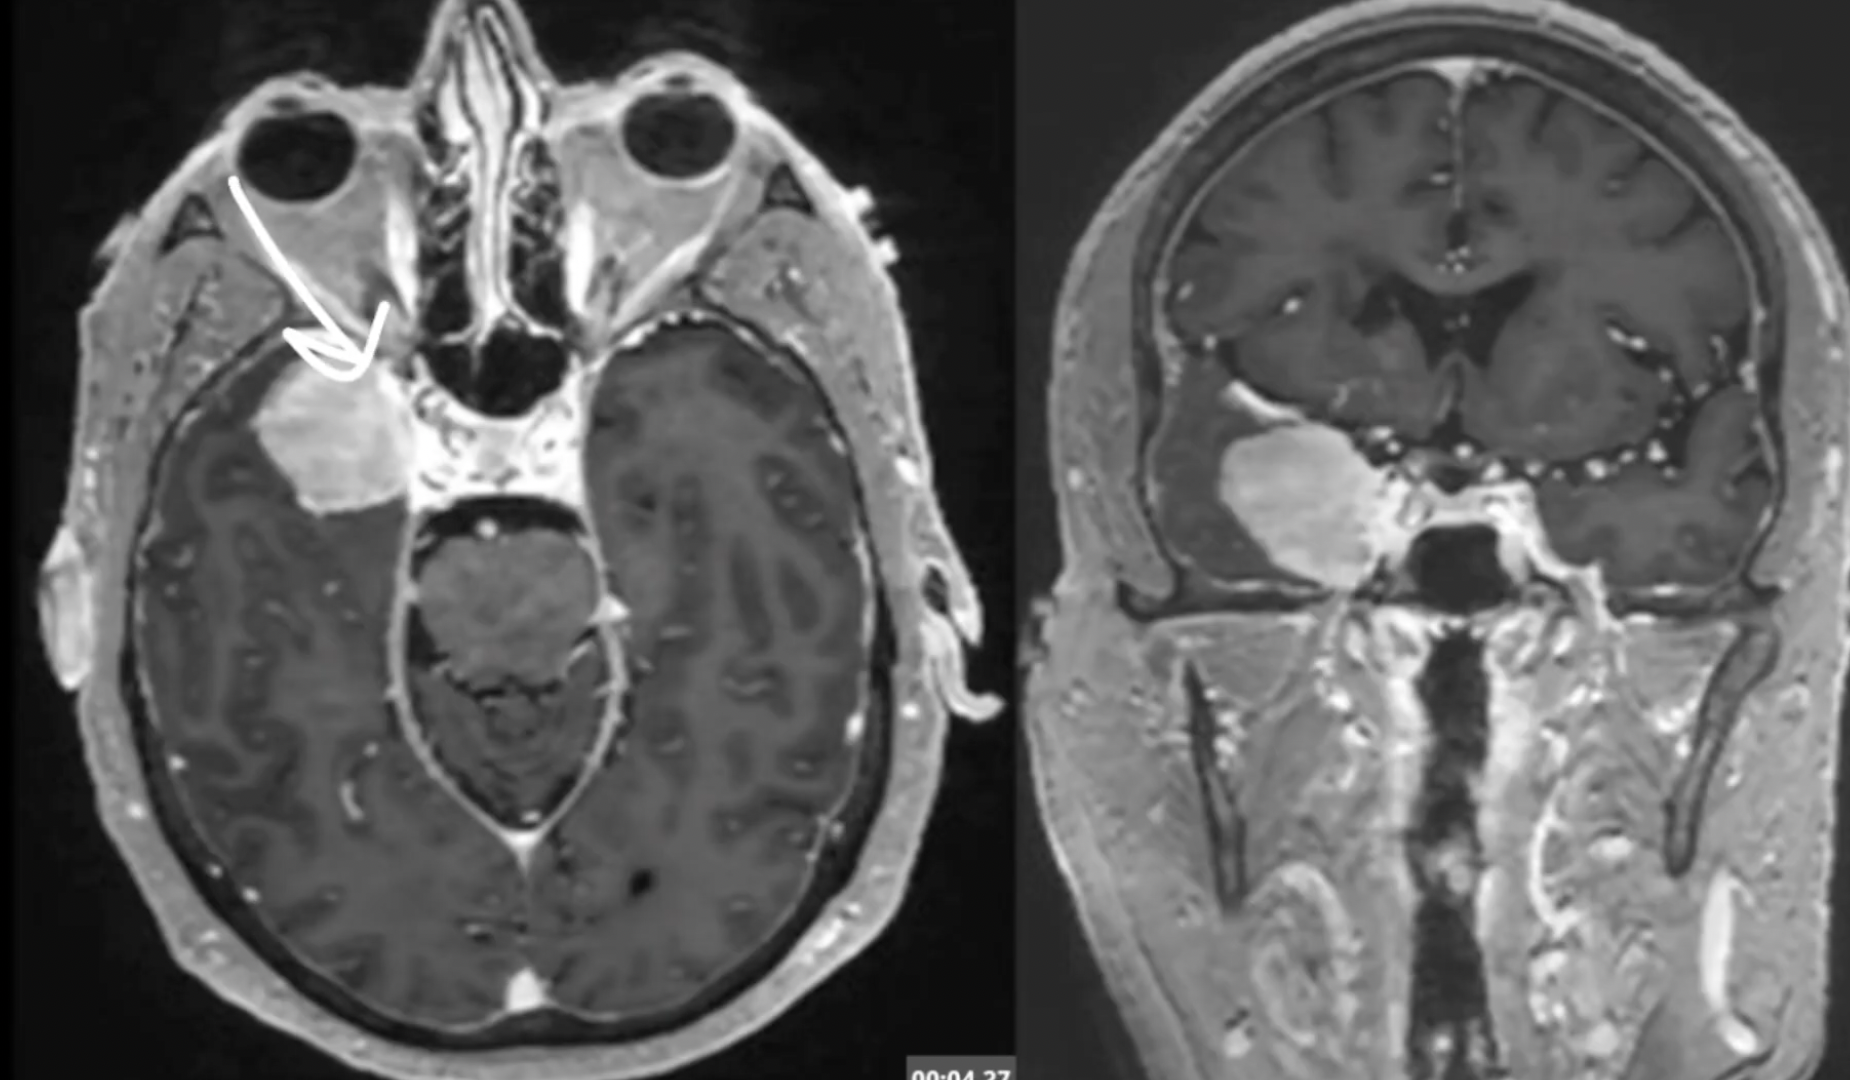

A way to improve skull base surgery through the advanced application of endoscopic techniques.